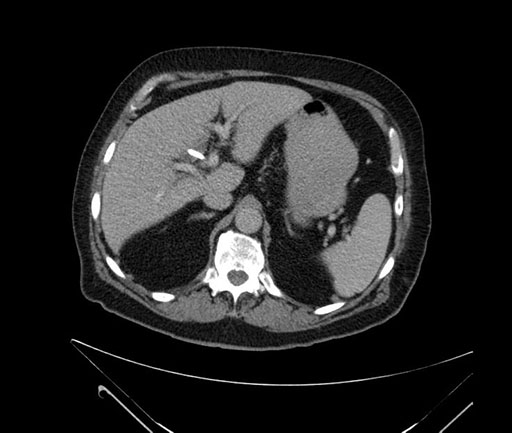

Axial - 3 months prior